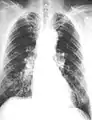

The abnormal chest x-ray and its interpretation remain the most important factors in establishing the presence of pulmonary fibrosis.[12] The findings usually appear as small, irregular parenchymal opacities, primarily in the lung bases. Using the ILO Classification system, "s", "t", and/or "u" opacities predominate. CT or high-resolution CT (HRCT) are more sensitive than plain radiography at detecting pulmonary fibrosis (as well as any underlying pleural changes). More than 50% of people affected with asbestosis develop plaques in the parietal pleura, the space between the chest wall and lungs. Once apparent, the radiographic findings in asbestosis may slowly progress or remain static, even in the absence of further asbestos exposure.[26] Rapid progression suggests an alternative diagnosis.

61 yr old working industrially with asbestos for decades.